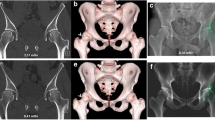

Torsion measurements

Two readers (G.K. and S.A.) with 3 and 5 years of experience in musculoskeletal imaging measured the lower limb torsion in all data sets using a technique modified from Waidelich et al [20]: Femoral torsion was measured as the angle between a line central through the femoral head and central through the greater trochanter (femoral neck) and a second line along the posterior margin of the femoral condyles. Tibial torsion was measured between a line along the posterior margin of the tibial plateau and a line central through the tibial and fibular parts of the ankle joint. Overall torsion of the lower limb was measured between the femoral neck and ankle joint (Fig. 2).

CT torsion measurement of the lower limb using a technique modified from Waidelich et al [20] and measurement of image noise in fatty tissue at standardized anatomical landmarks

As an objective measure, the image noise in fatty tissue was captured within a 2-cm2 circular region of interest (ROI) tool at standardized anatomical landmarks next to the rima ani (hip scan), next to the medial tibia plateau (knee scan), and next to the Achilles’ tendon (ankle scan) (Fig. 2). In addition, both readers (G.K. and S.A.) rated their subjective diagnostic confidence level regarding the identification of the relevant cortical bone in every simulated data set as well as in the original data set on a 5-point Likert scale from “poor” (1) to “excellent” (5). The hip, knee, and ankle scans were rated independently.